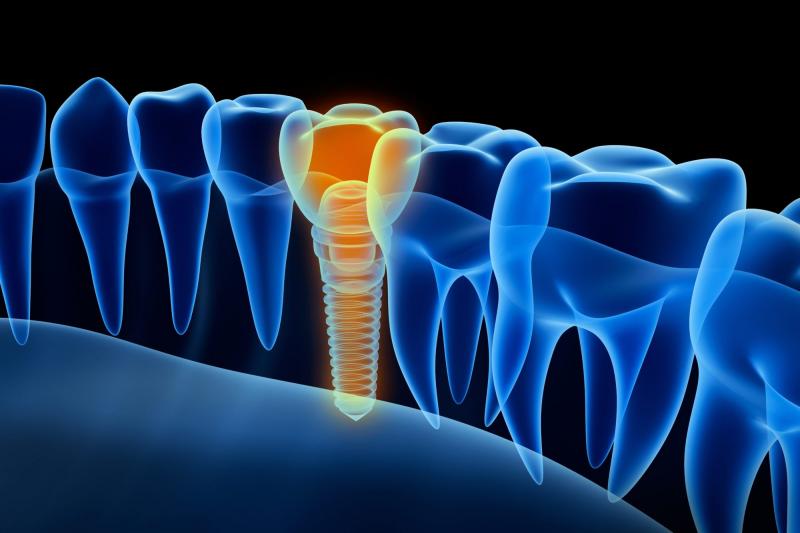

Automated dental care systems, also known as dental turbines, are miniature high-speed electric motors equipped with hand pieces or attachments used in dental procedures such as dental cavity preparation and root canal treatment. Automated dental care systems offer increased control, speed, and precision compared to traditional dental hand pieces and improve clinical outcomes and patient comfort. The increasing prevalence of tooth decay and other dental diseases is propelling the demand for automated and advanced dental treatment procedures. Automated dental care systems allow dental professionals to efficiently perform procedures that require high-speed cutting or grinding such as cavity preparations and crown preps, thus reducing treatment time.

Reduced treatment time and improved effectiveness provide a strong market opportunity for automated dental care systems. Using automated dental care systems rather than traditional low-speed hand pieces enables dental professionals to complete cavity preparations, crown preps, and other procedures involving cutting or grinding of hard dental tissues more quickly. This translates to reduced time that patients have to spend in dental chairs undergoing uncomfortable treatments. Automated dental care systems also provide more consistency and precision compared to low-speed hand pieces, allowing dental professionals to precisely shape dental tissues and complete procedures more effectively in fewer visits or interventions. The time and cost savings for both dental professionals and patients are driving increased adoption of automated dental care systems.